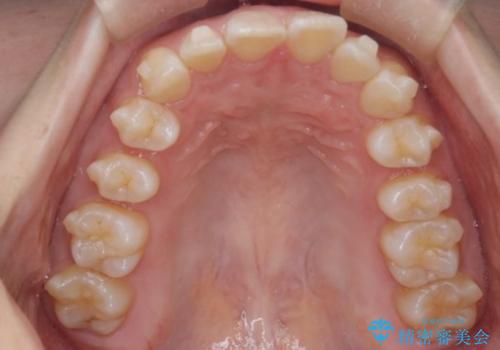

- 上の前歯の出っ歯と前歯の深い咬み合わせを治したいとのことで来院された患者様です。

上顎の歯は後方移動とIPR(歯と歯の間を削る)によって口元が引っ込むように、下顎は歯列全体の拡大とIPRによって上顎とバランスよく咬み合うように設計し、インビザラインにより治療を行うこととしました。

上顎歯列の後方への移動量が多く、右側の奥歯の咬み合わせを改善する必要もあったため、治療には長期間を要しました。